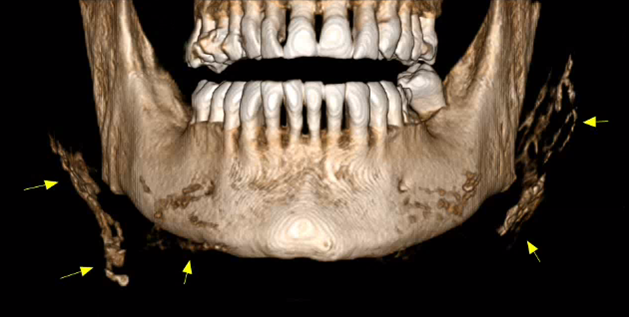

Ένα παράδειγμα είναι η γενειοπλαστική, όπως φαίνεται στην παρακάτω περίπτωση.

Απεικονιστικά παρατηρούνται πολλαπλές συρρέουσες υπέρπυκνες δομές μικρών διαστάσεων εντός των μαλακών μορίων και πλησίον του εξωτερικού τους περιγράμματος.

Εκτός από τις παραπάνω ελάχιστα επεμβατικές τεχνικές, στις απεικονίσεις της τραχηλοπροσωπικής χώρας μπορεί να συναντήσουμε και τα αποτελέσματα πιο επεμβατικών τεχνικών, όπως διάφορες μορφές πλαστικής χειρουργικής με χρήση ενθεμάτων σιλικόνης.